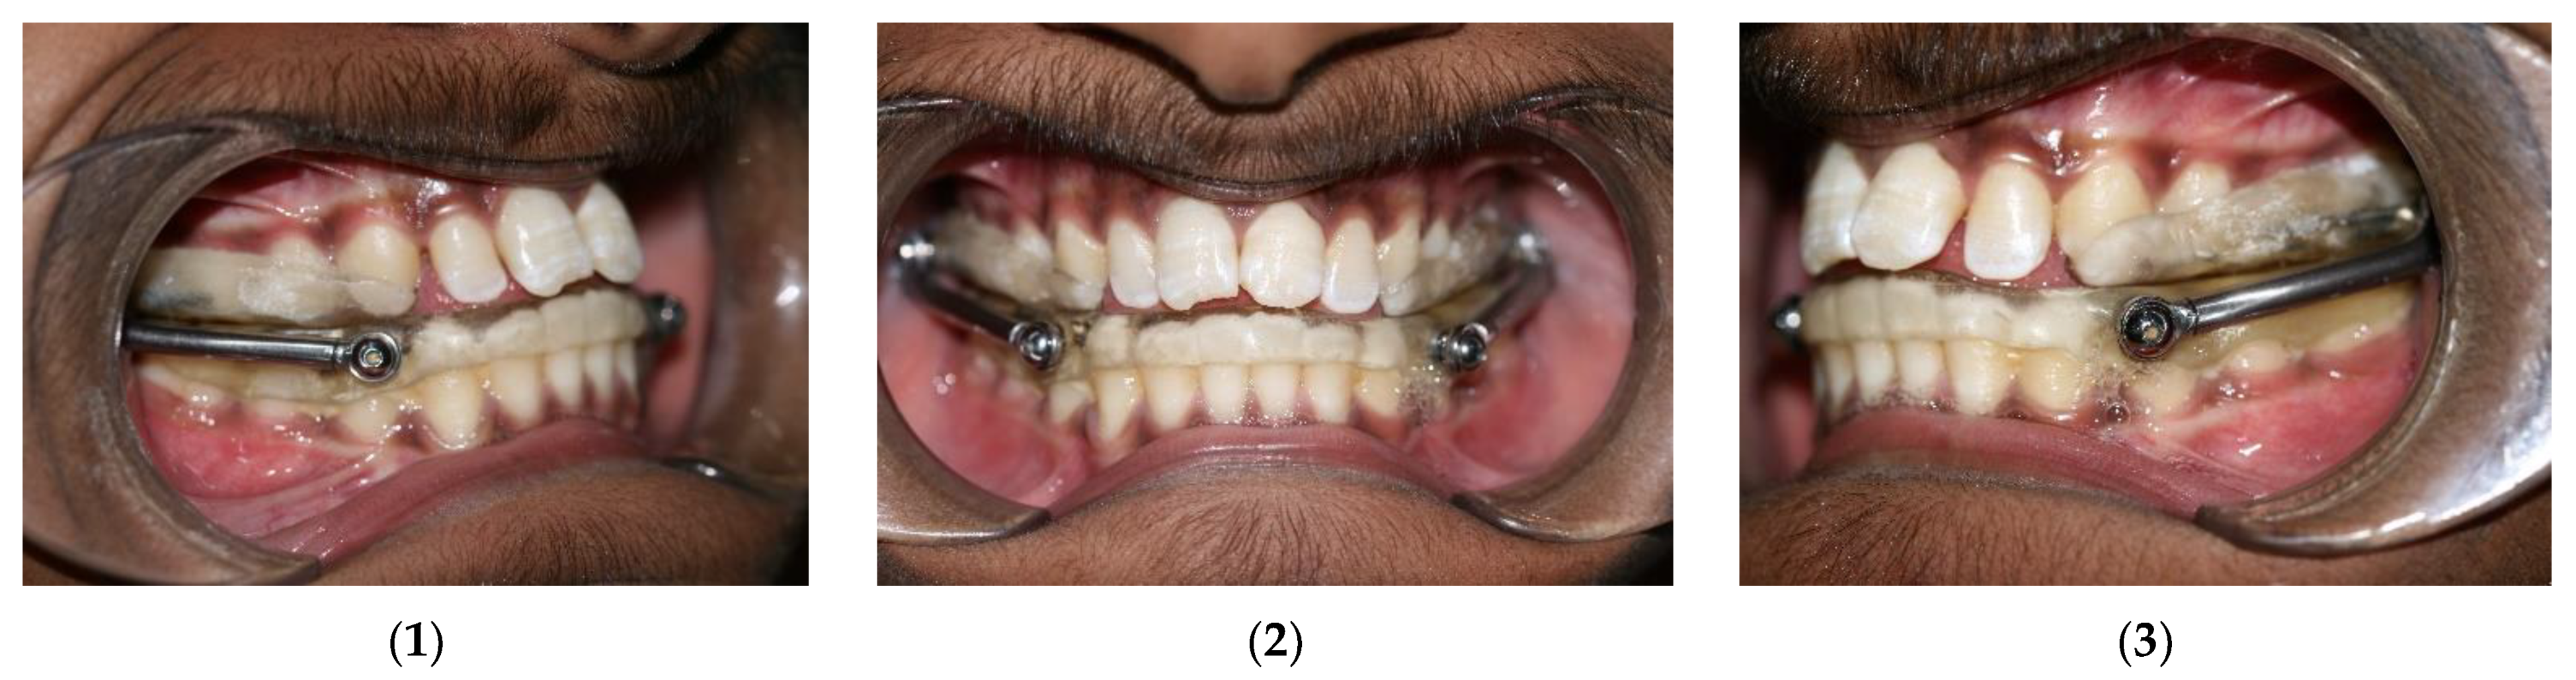

2. Materials and Methods